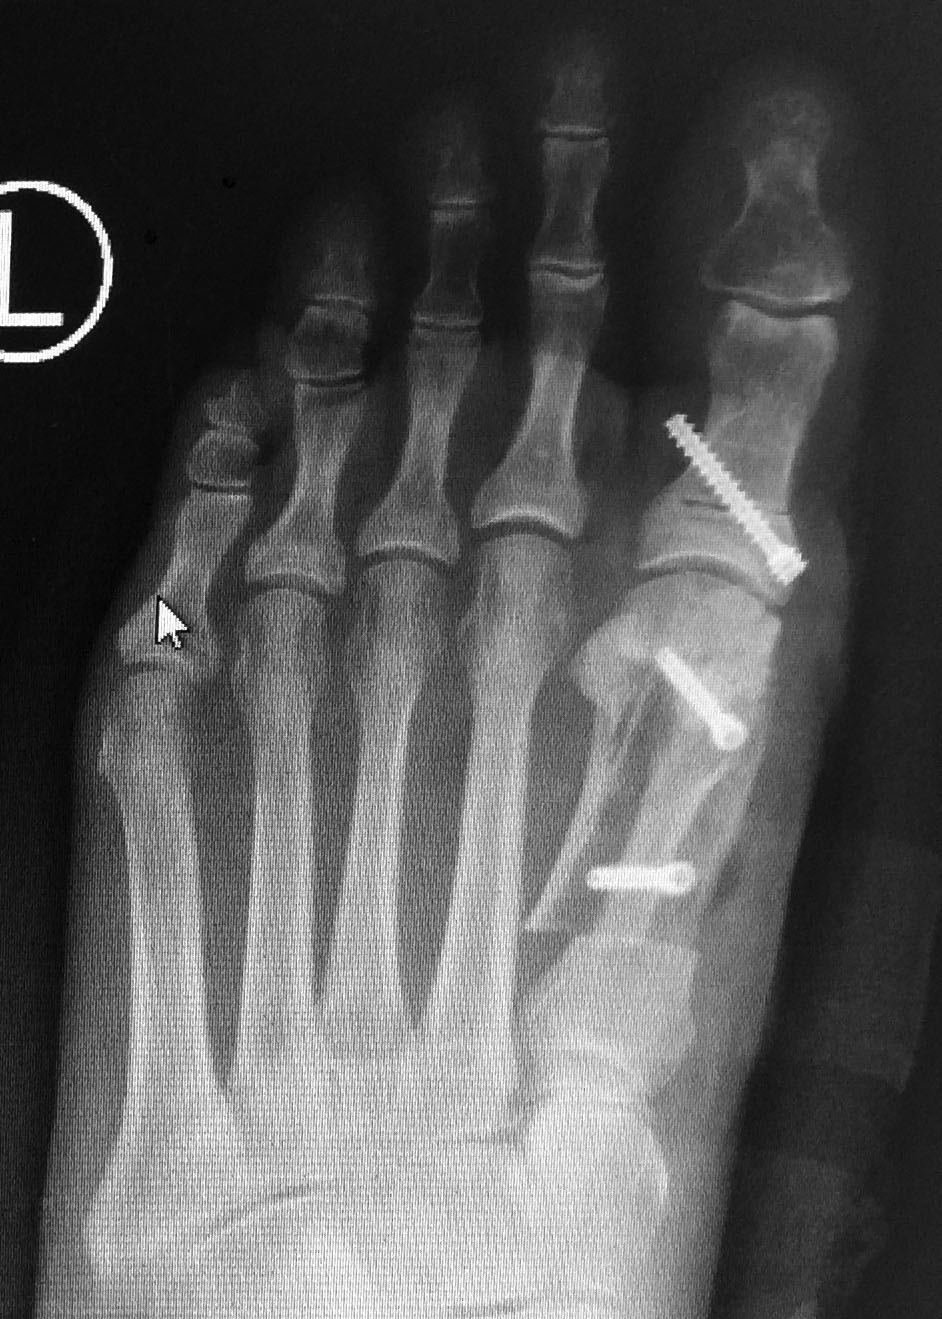

Scarf and Akin Procedure.

Cots are made in the bone, and screws are used to keep the realigned bones in place whilst the bones heal in the correct position.